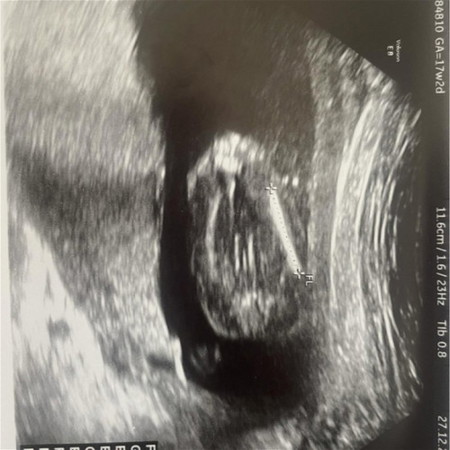

อัลตราซาวเพศ

เมื่อวานซาวด์มา น้องก้อหนีบไม่ให้ดู ลุงหมอรอลุ้นซาวด์สิ้นเดือน 21วีคอาจจะอ้าให้เห็นแล้ว